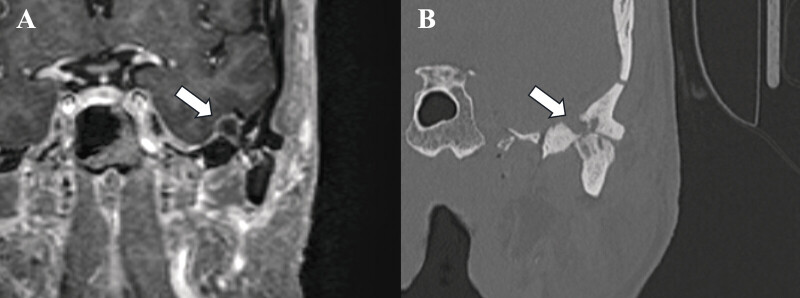

Case presentations: Three patients presenting with otalgia and TMJ tenderness were found to have intracranial cysts communicating with the TMJ. Two patients had been transferred with suspected intracranial abscesses; one presented for workup of headache and trigeminal neuralgia. All three demonstrated elevation of inflammatory markers. Two patients had TMJ aspiration, notable for leukocytosis and crystalline deposition, another had frank purulence. One patient demonstrated pneumocephalus within the cyst on imaging. The intracranial cysts ranged from 1.2 to 3.3 cm in maximum diameter, with their bony defects ranging from <1 to 4 mm. Two patients underwent craniotomy, cyst resection, and repair of the middle fossa defect, while the third opted for observation. Pathology of the white gelatinous fluid within the two resected growths demonstrated benign cysts.